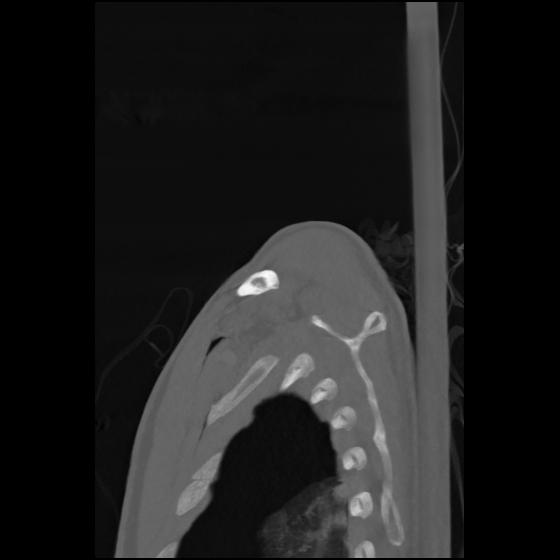

24 ANGIO,CE,Sag-MIP,5.000,ANGIO,Sag-MIP,